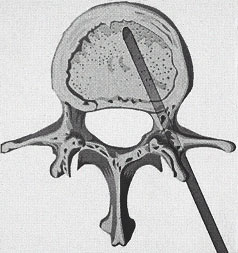

Abb.1oben

Schematische Darstellung des Einbringens der Punktionskanüle in den Wirbelkörper durch den Wirbelbogen (transpedikulär)